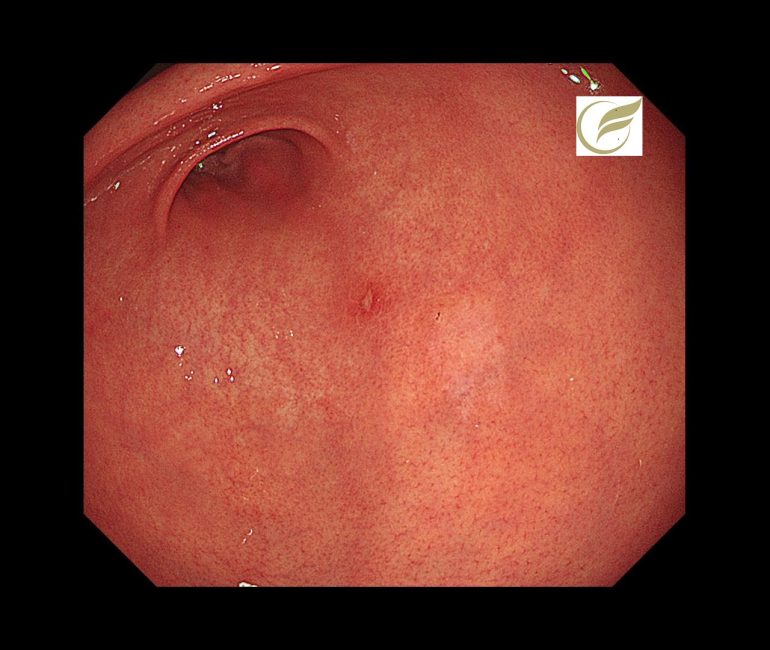

初期像は、内視鏡でわずかな退色調の平坦・陥凹病変として認められることが多く、早期診断には内視鏡観察が必要です(4)。

以下は当院で経験されたピロリ陰性の印環細胞癌(早期癌)の症例です。内視鏡治療で治癒が得られています。